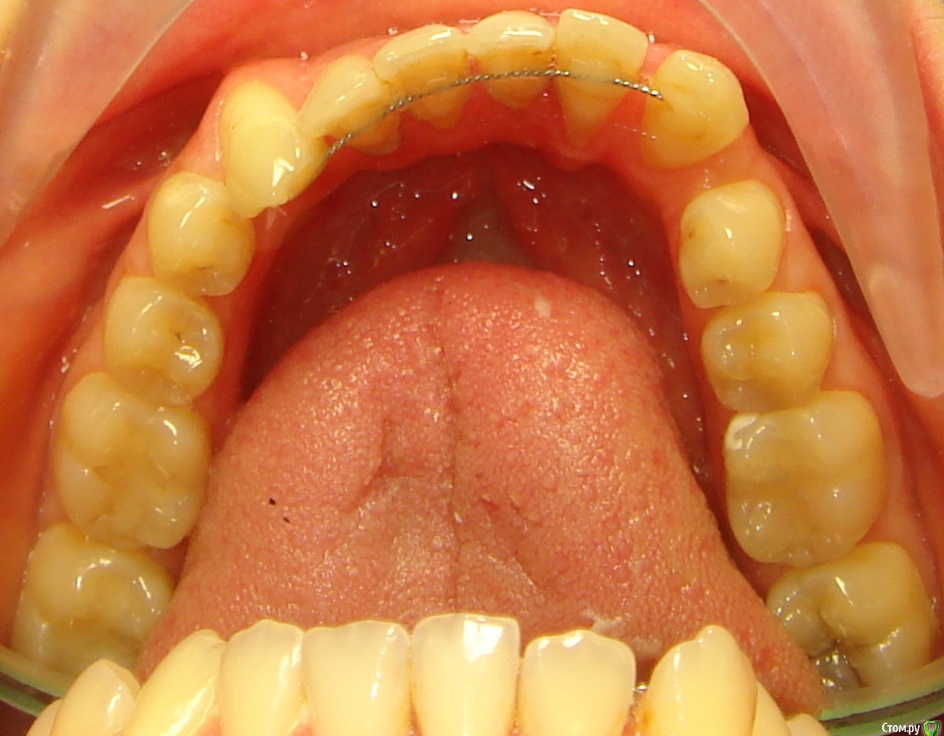

Opdihatop Опубликовано 4 марта, 2017 Поделиться Опубликовано 4 марта, 2017 И снова здравствуйте, коллеги. Вот такой вот случай к рассмотрению. Много лет назад пациентка уже проходила "камуфляжное" лечение. Со слов пациентки оно было закончено с передним открытым прикусом. Сейчас ситуация такая. Пациентка думает над ортохирургией, но меня смущает фронт н/ч. И по снимкам и по ситуации во рту корни 32, 31, 42, 43 зубов фенестрировали лингвальную кортикалку почти на всем протяжении, 33 - вестибулярную. Вопрос вот в чем: что делатьс этими зубами? Возможно ли их поставить на место? Или лучше не трогать, дольше простоят? Ссылка на комментарий

Brigita Опубликовано 4 марта, 2017 Поделиться Опубликовано 4 марта, 2017 она, кстати, везде язык прокладывает на фото. Наверно и в хирургии смысла не будет... Ссылка на комментарий

Opdihatop Опубликовано 29 мая, 2017 Автор Поделиться Опубликовано 29 мая, 2017 Как? Очень просто, "ДОЛЕЧИВАТЬ"! Тут фенестрация произошла из-за невылеченного инфантильного типа глотания и очень качественного (тут без сарказма) несъемного ретейнера. Исправь прошлый доктор язык, или поставь ретейнер хуже, так чтобы он его давление не выдержал и сломался, было бы все иначе. Ссылка на комментарий